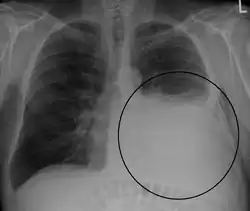

Massive left-sided pleural effusion (whiteness) in a patient presenting with lung cancer.

Massive pleural effusion, later proven to be hemothorax in a South Indian male.